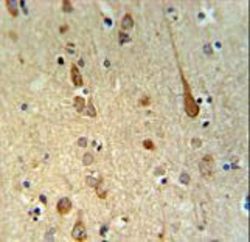

Immunohistochemistry

LS-C165910 IHC